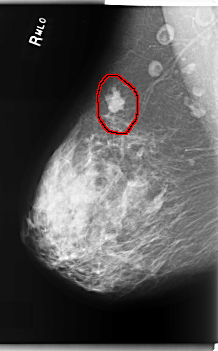

FILE: C_0208_1.RIGHT_MLO.OVERLAY

TOTAL_ABNORMALITIES 1

ABNORMALITY 1

LESION_TYPE MASS SHAPE IRREGULAR MARGINS MICROLOBULATED

ASSESSMENT 5

SUBTLETY 5

PATHOLOGY MALIGNANT

TOTAL_OUTLINES 1

BOUNDARY